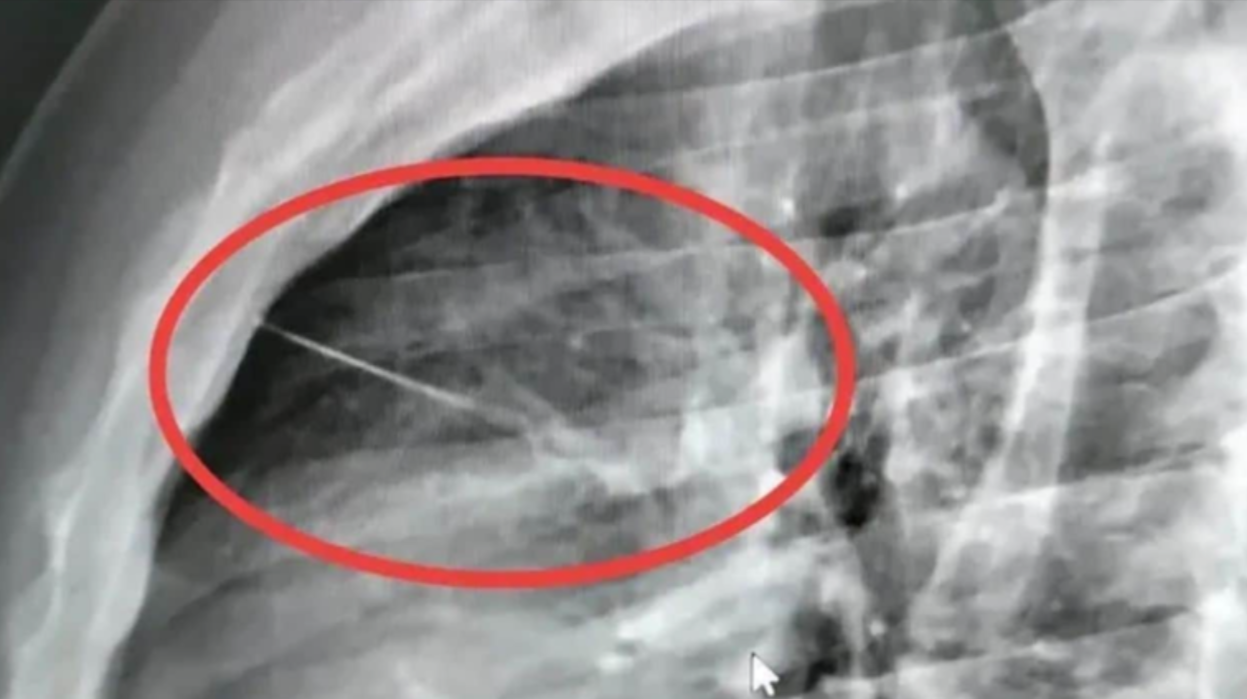

泰國武里南府發生罕見意外,一名男子因胸口劇痛求醫,經X光檢查後,醫生震驚發現其胸腔內竟藏有一根長約7厘米的縫衣針,位置極接近心臟,隨時有生命危險。男子其後緊急接受手術取出縫衣針,但手術風險極高,術後情況仍然危殆。

醫院為事主進行X光檢查後,發現一枚細小而尖利的異物位於心臟附近,隨即將他轉送至另一所醫院接受緊急手術。主刀醫生形容,取出縫衣針的手術過程複雜且高風險,稍有差池便可能危及性命。